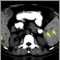

Imaging tests to diagnose colorectal cancer include: